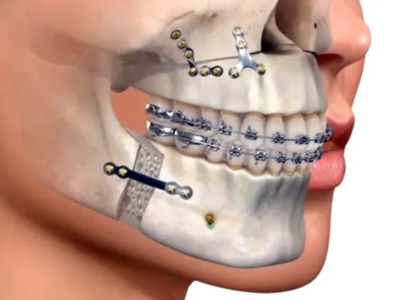

Oral & Maxillofacial Surgery in Eluru

We provides safe and advanced oral & maxillofacial surgical care, including wisdom tooth removal and minor oral surgeries.